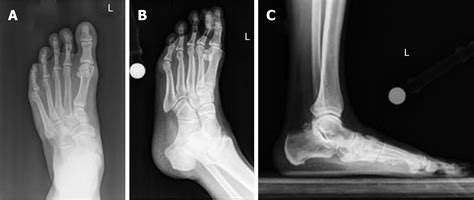

To diagnose osteoarthritis in feet, a medical professional will typically perform a physical examination, checking for range of motion, tenderness, and signs of deformity. Imaging tests are essential to confirm the diagnosis and assess the severity of cartilage loss.

X-Rays To view joint space narrowing and bone spurs.